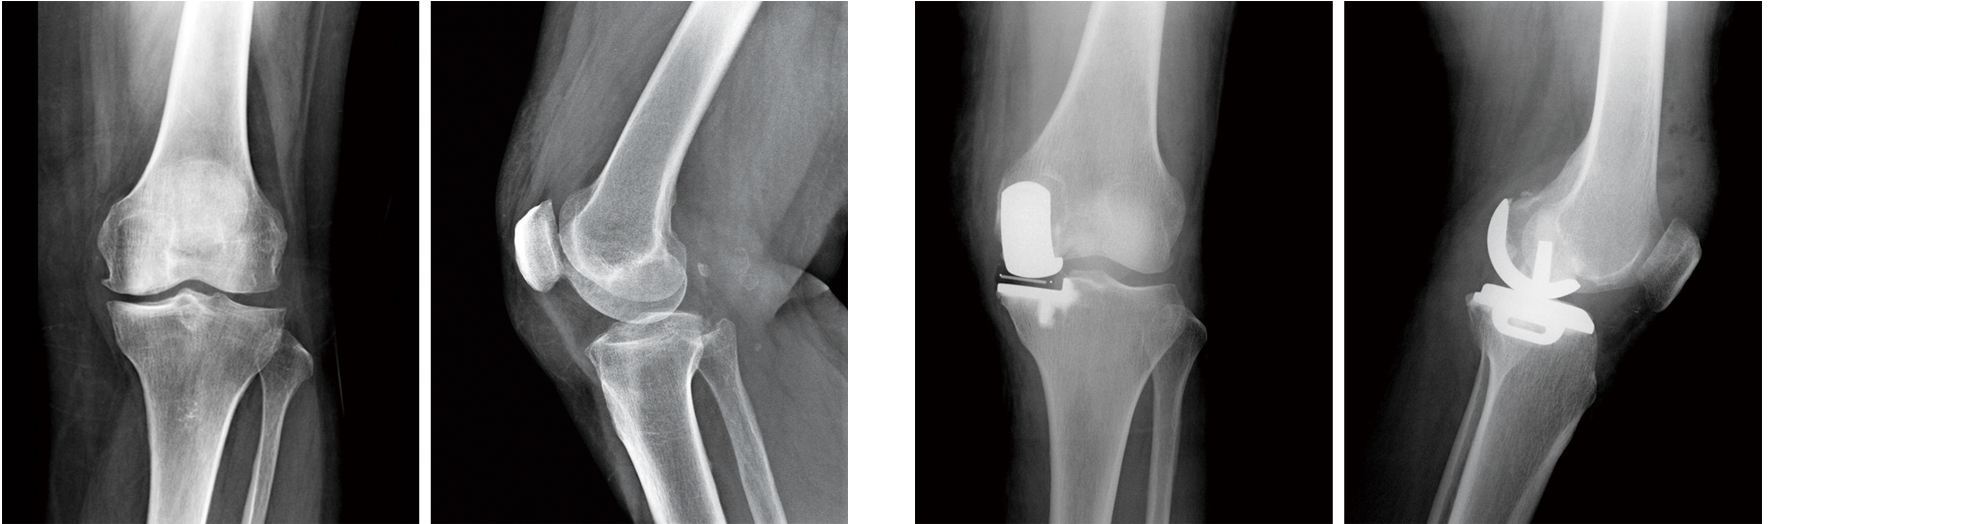

78岁老人膝关节骨性关节炎兴城市人民医院首例单髁置换

膝关节的x线检查有助于判断是否患上膝关节骨性关节炎,是首选的最简单

膝关节正常x线片膝关节的x线检查有助于判断是否患上膝关节骨性关节炎